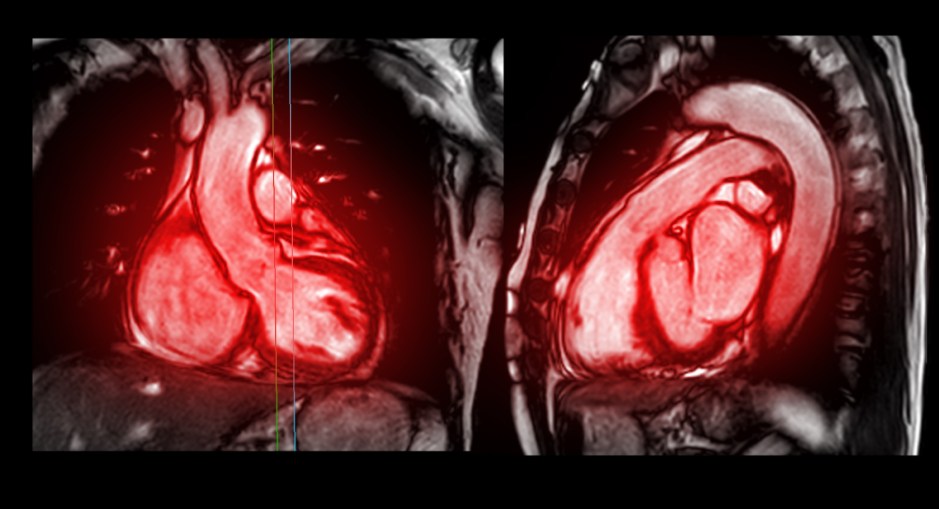

Research funded by the British Heart Foundation using novel cardiac imaging techniques was described in a recent article in Circulation. These techniques, such as quantitative perfusion cardiac magnetic resonance imaging and cardiac diffusion tensor imaging, can detect pre-clinical hypertrophic cardiomyopathy (HCM) before the development of any thickening in the heart.